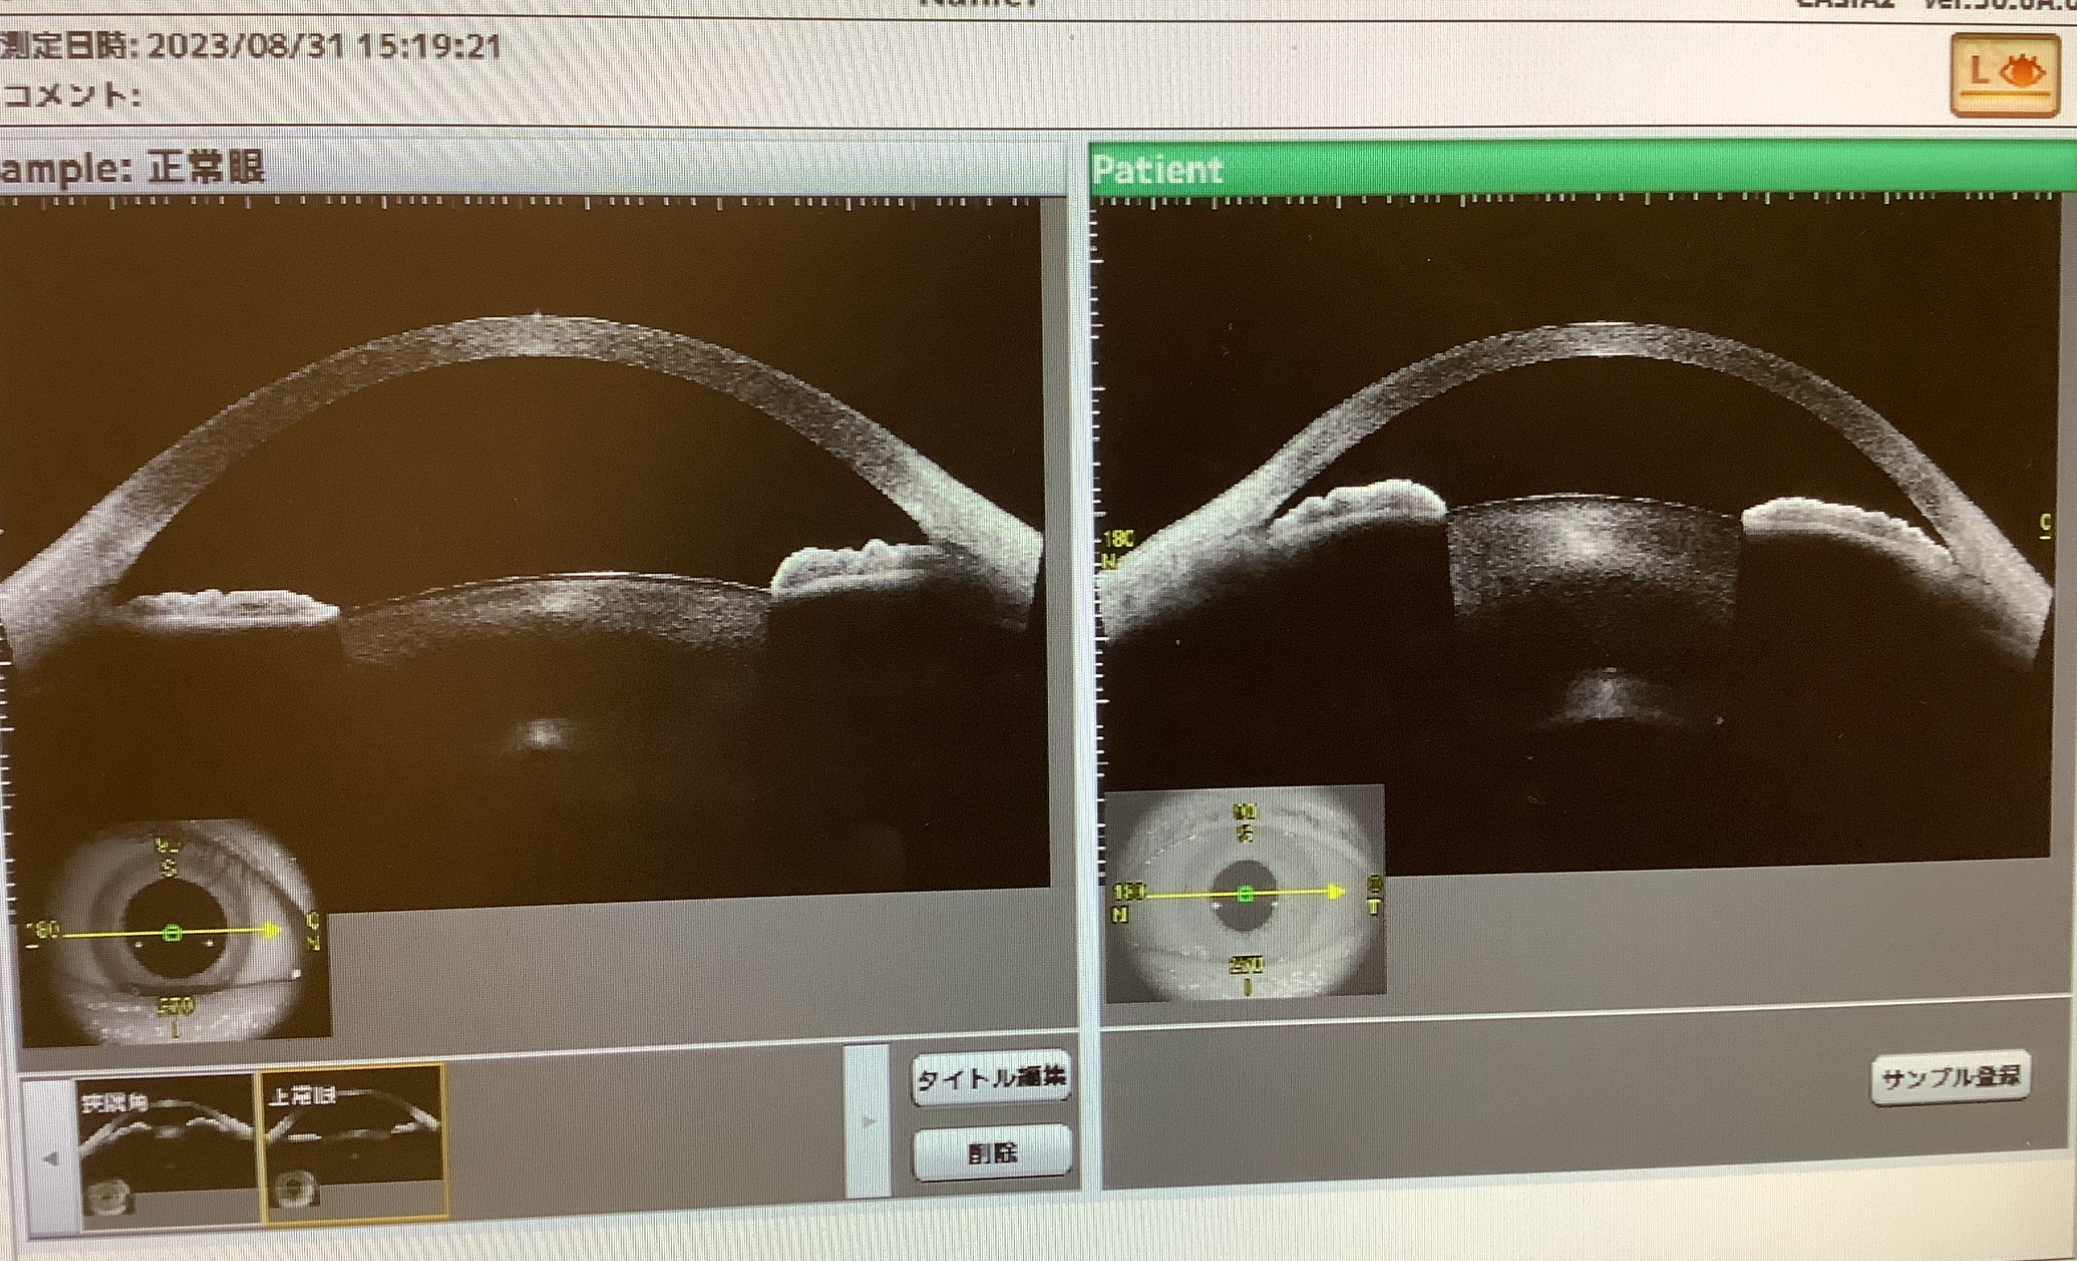

・白内障の手術を勧められたのは?→隅角が狭めで、急に眼圧が上がってしまう“緑内障発作”を起こしやすそうな眼なので、その発作を防ぐ治療として、白内障の手術が有効なため。

というような説明をさせていただきましたが、この方の眼は、軽度の白内障と狭隅角症という状態で、治療をするなら白内障手術が望ましいと思われました。ただ、隅角がすごく狭くて、いつ緑内障発作が起こってもおかしくないというほどではなく、視力も困っていないそうで、数か月毎に様子を見て考えましょうということになりました。

狭隅角症の人は、多かれ少なかれ緑内障発作のリスクを持ちことになりますが、必ず起こすものでもないので、視力が良好なうちは治療に踏み切る判断が難しいかと思います。大事なのは、治療の必要性とそのままの危険性を十分理解した上で、納得して方針を選択することと、もし万が一、経過中に発作を起こしてしまったら、なるべく早めに受診することです。